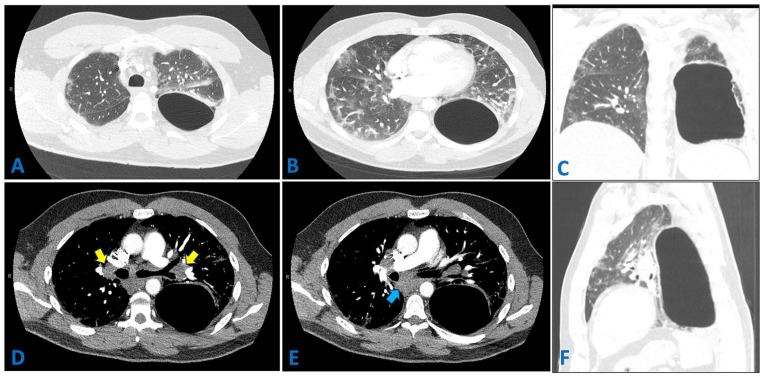

Sarcoidosis is a systemic granulomatous disease that predominantly affects the lungs. However, its presentation as a giant pulmonary bulla is exceptionally rare. Its association with COVID-19 has raised new concerns regarding disease exacerbation and misdiagnosis. We report a case of a 38-year-old man who developed a large left lower lobe bulla in the context of recent COVID-19 infection. Initial misinterpretation of the bulla as loculated pneumothorax nearly led to an unnecessary chest tube placement. A subsequent thoracotomy with lobectomy revealed nonnecrotizing granulomas, confirming sarcoidosis. The patient showed spontaneous remission without requiring treatment. This case highlights the importance of multidisciplinary discussions in atypical lung presentations to prevent mismanagement.